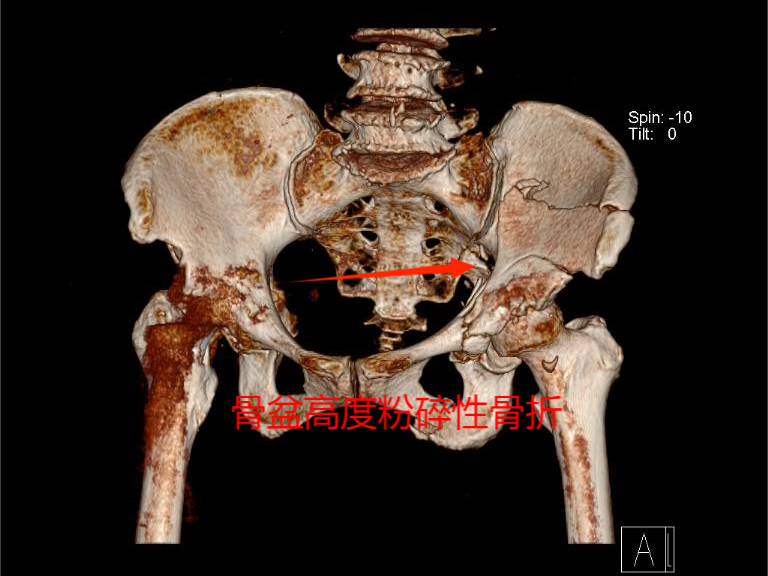

· 病例三

患者,女性,70岁,因“车祸伤致头部、腰部及左髋部疼痛2小时。”入院。辅助检查:入院诊断:骨盆骨折(Tile C型)。

术前图片: